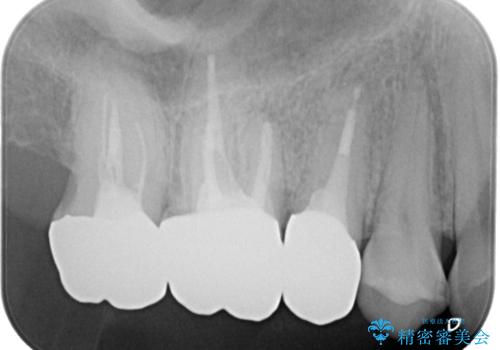

保険で治療した歯が欠けた。オールセラミッククラウンによる修復

- 以前、他院で保険治療の被せ物を入れた歯が欠けてしまったことを主訴に来院されました。

その他の歯も適合が悪く治療が必要でしたので、3歯まとめて治療を行いました。

歯肉縁下マージンに対して矯正的挺出などの治療の選択肢や、根管治療の提案をしましたが、患者様との話し合いにより歯冠修復のみ行なっております。